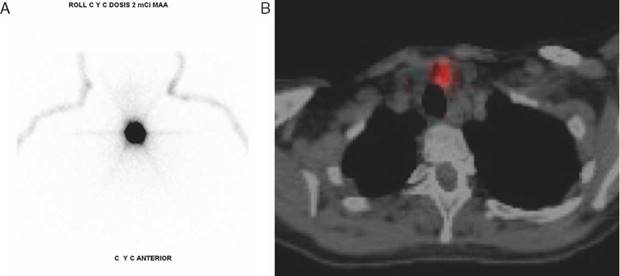

Para precisar la zona anatómica se realizó tomografía computada (TC) con contraste de cuello, identificando dos lesiones sugestivas de adenopatías metastásicas sobre la cara lateral izquierda de la tráquea, y descartando que se tratara de una recaída con invasión a la vía aérea o digestiva (fig. 2). Por tratarse de una lesión de pocos milímetros y no palpable se decidió la extirpación quirúrgica radioguiada con técnica ROLL. La tarde previa a la cirugía, bajo visión ecográfica con equipo General Electric Logiq F8, dotado de un transductor de 13 Mhz se marcó la lesión a resecar con 2 mCi de 99m-Tc-MAA. Seguidamente, se realizaron imágenes SPECT y SPECT/CT, con equipo Discovery NM/CT 670 que combina la imagen anatómica y funcional del SPECT y del CT multicanal de alta tecnología (fig. 3).

Figura 3 Marcación con Tc-99m-MAA: A. Imagen planar con SPECT donde se observa lesión focal. Infortunadamente con esta imagen solo se puede verificar si la inyección es de buena calidad, ya que no se puede determinar ninguna referencia anatómica. B. Imagen axial fusionada con SPECT/CT en la que se localiza lesión nodular pretraqueal izquierda correspondiente a recaída ganglios subcentimétricos de grupo vi.

Se realizaron imágenes estáticas de la región anterior del cuello en matriz de 128 x 128 con zoom de 1,23, con lo que se observó la localización focal. Entonces se procedió a adquirir SPECT/CT en matriz de 128 x 128 zoom de 1. Técnica body contourd, step and shot con tomas de 10 segundos. Procediendo a la reconstrucción tridimensional: coronal, sagital y axial del lugar de la inyección de radiofármaco, campo de cabeza y cuello.